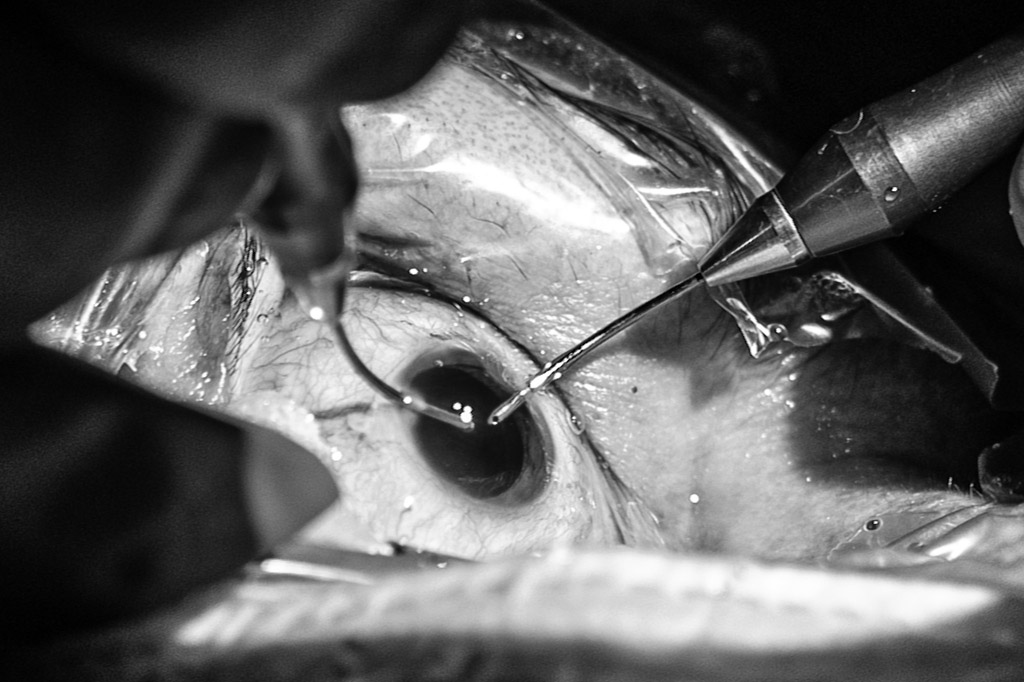

W mojej pracy stosuję najskuteczniejszą i najmniej inwazyjną metodę operacji zaćmy jaką jest FAKOEMULSYFIKACJA. Technika ta w zaćmach niepowikłanych nie wymaga zakładania szwów, a zastosowane soczewki są zwijalne i wprowadzane do wnętrza gałki ocznej za pomocą 2,2 milimetrowego cięcia w rogówce.

W trakcie zabiegu wykonuje się 3 nacięcia w przezroczystej rogówce (cięcie główne – 2,2 mm oraz dwa cięcia boczne 1,0 mm) przez które wprowadza się do oka narzędzia chirurgiczne i substancje niezbędne podczas wykonywanego zabiegu. W trakcie zabiegu soczewkę własną usuwa się za pomocą ultradźwięków a na jej miejsce implantuje się sztuczną soczewkę wewnątrzgałkową.